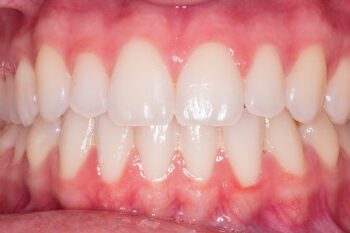

Colour

For cosmetics, the colour of the crown is the most important factor. It must blend in with the adjacent teeth nicely so that any observer is oblivious to the fact is it a false tooth. How do we get this right?

First of all, there are around 20 different shade tabs on a standard vita shade guide, and this will help us to choose the colour of your teeth and you must remember that each tooth does not just have one colour but a variety. See the shade guide below.

The picture below illustrates the different colours (hue), value (brightness) and chroma (intensity of colour) a tooth can have. Mimicking nature can be a very hard thing to do and that’s why you need to be sure you have picked a good dentist and also a good dental technician.